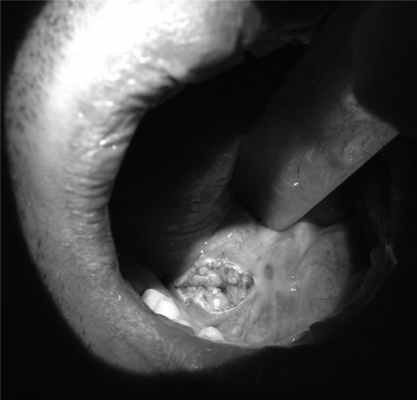

3. При невозможности удаления конкремента по изложенным выше методикам мы фиксировали его в протоке «корзиной», подтягивали максимально ближе в сторону устья и, ориентируясь по рабочей части эндоскопа и «корзины», как по проводнику, проводили сиалодохотомию (рис. 3), с последующей экстракцией камня (127 пациентов).

Рис. 3. Внутриротовой доступ к ампулярной части главного выводного протока подчелюстной слюнной железы.

При удалении конкремента из околоушной слюнной железы точную локализацию камня определяли методом диафаноскопии, используя для этой цели световод сиалоскопа, установленный в протоке непосредственно перед конкрементом (рис. 4). Затем осуществляли чрезкожный хирургический доступ в проекции конкремента длиной от 1 до 1,5 см, выделяли проток, ориентируясь при этом на световое пятно в строме оперируемой железы, рассекали стенку протока и затем удаляли камень. По данной методике в нашем центре прооперированы 8 пациентов. При этом для снижения риска интраоперационной травматизации ветвей лицевого нерва данные этапы операции проводили в условиях интраоперационного нейромониторирования (рис. 5).

Рис. 4. Диафаноскопия ОСЖ с использованием сиалоэндоскопа диаметром 1,6 мм. а — определение свечения сиалоскопа через кожный покров; б — вид хирургического доступа к выводному протоку околоушной слюнной железы над конкрементом.